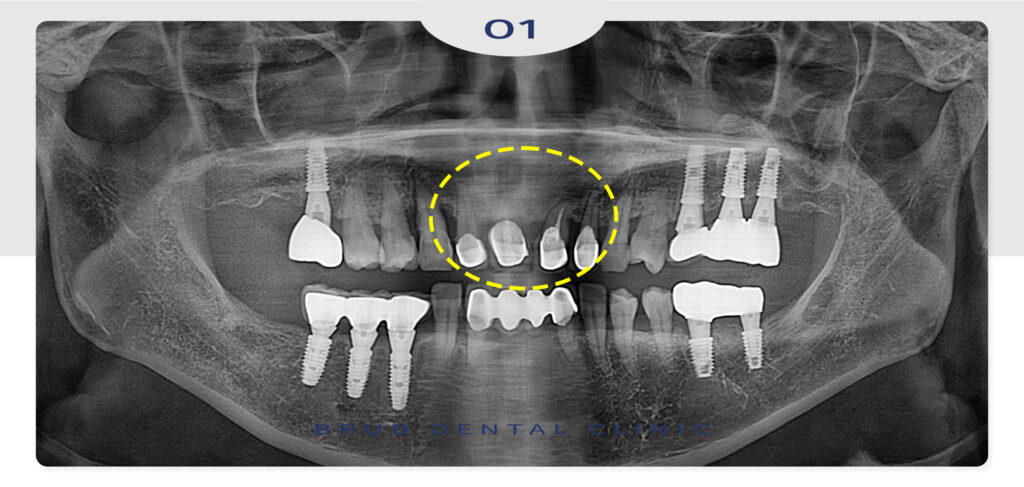

25.09.13

위쪽 앞니 중 씌워져 있던 4개와

양 옆의 상태가 좋지 않았던 송곳니까지

총 6개를 발치하고 비용적인 부분을 고려해

3개의 임플란트를 식립하기로 하였습니다.

더불어 골흡수가 심하게 진행된 부위는

뼈이식을 함께 진행하였는데요.